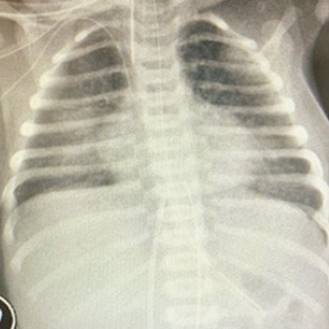

Se conectó a asistencia ventilatoria mecánica en modo asistido y controlado con PIM 16 PEEP 6, PMVA 9, FIO2 25% y volumen corriente 5 mL/kg. Se solicitó paraclínica (Tabla 1) y radiografía de tórax (Figura 1), se iniciaron en forma intravenosa: antibióticos empíricos (ampicilina a 400 mg/kg/día, gentamicina a 4 mg/kg/dosis cada 24 horas); antivirales (aciclovir a 20 mg/kg/dosis cada 8 horas) e inotrópicos (dobutamina a 10 mcg/kg/min), este último por 24 horas. A las 8 horas, con estabilidad clínica, se realiza punción lumbar (Tabla 1).

Figura 1: Radiografía de tórax con infiltrado intersticial bilateral difuso, sin foco claro de consolidación.